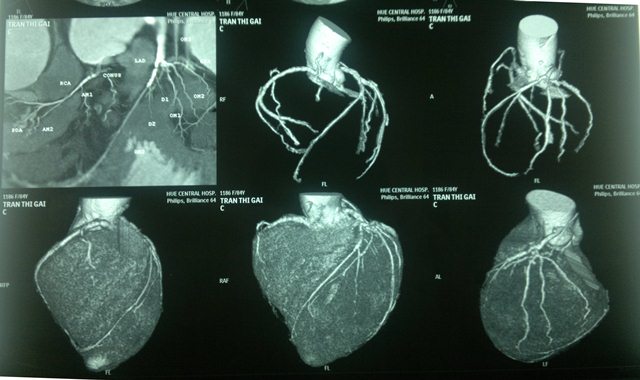

Phim CT 64 hẹp đa nhánh mạch vành

1. Phình động mạch chủ lên

2. Phình tách động mạch chủ trên phim CT 64

3. Thất phải lớn trong Fallot 4